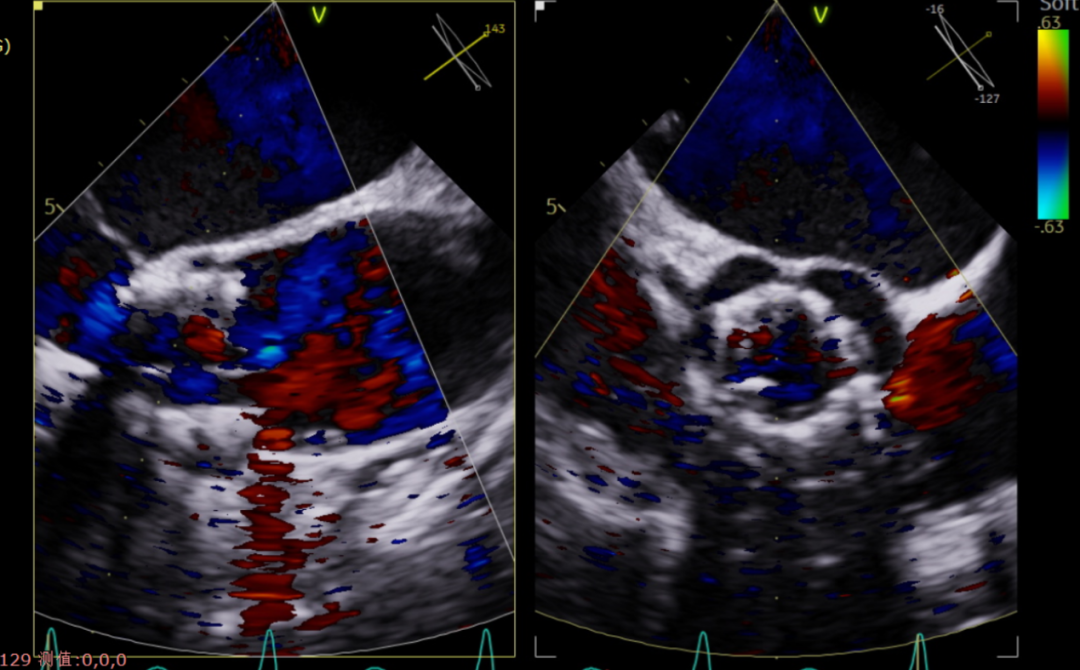

术后超声影像图